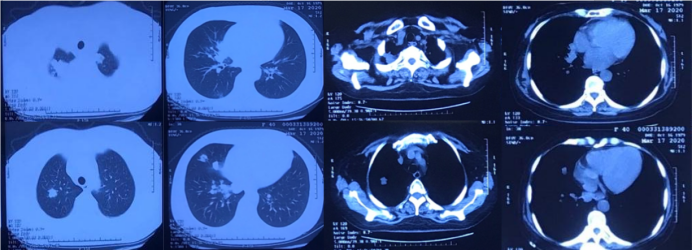

患者半年前因“成人Still病”开始口服激素(醋酸泼尼松片20 mg qd)及环孢素(50 mg bid)治疗,用药期间患者出现咳嗽、咳痰症状,黄白色黏痰,量不多,不易咳出,无胸闷、气短、胸痛、咯血等不适,就诊于北京某医院,完善胸部CT示“双肺多发肿块影及结节影,部分内伴空洞”,该院考虑真菌感染,予口服伏立康唑治疗1周。用药后患者咳嗽、咳痰症状一度缓解。自2020年2月开始,患者咳嗽、咳痰加重,间断出现发热,体温最高可达40℃,伴有畏寒,无寒战、呼吸困难等其他症状,调整激素为早晚各一次(醋酸泼尼松片10 mg/次),但患者体温控制较差,于3月15日(图1)及4月20日(图2)复查胸部CT检查,提示双肺多发肿块影及结节影,部分内伴空洞形成,病灶有增大、增多趋势。为求进一步诊治收入我院。

图1  患者胸部CT(2020-03-15)

胸部CT(2020-03-17):双肺多发肿块影及结节影,较大者大小约为3.7  cm×2.7 cm,部分内伴空洞。胸部CT(2020-04-20)示:双肺多发肿块影及结节影,较大者大小约为9.68 cm×5.4 cm,部分内伴空洞,与前片对比,病灶明显增大、增多;心包少量积液。